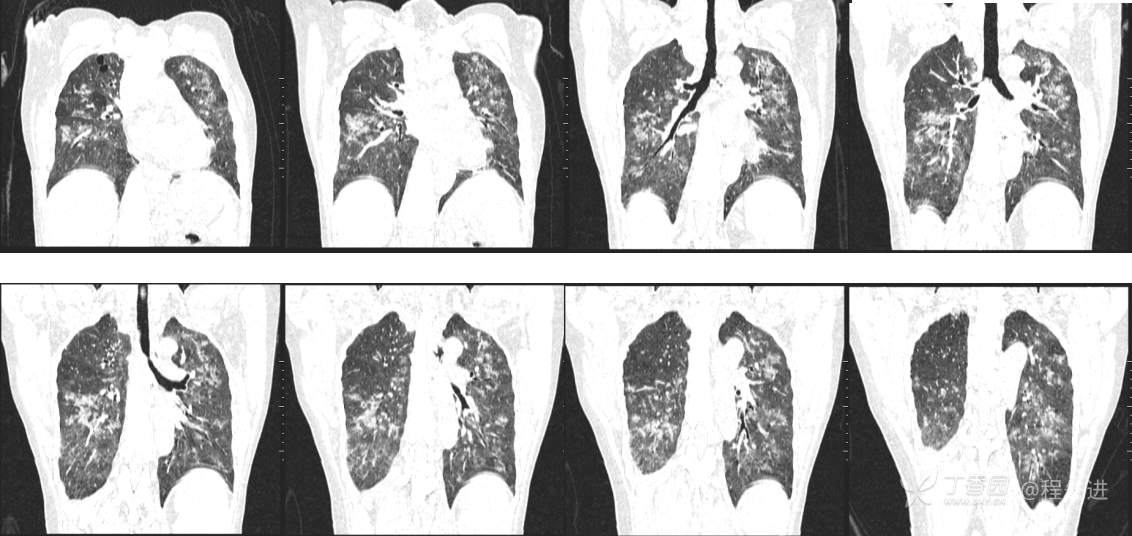

7月特别精彩病例|右肾移植术后咳嗽并气促20天,有重点病史,让诊断变简单|结果公布

主诉:咳嗽并气促20天

现病史:患者20天前无明显诱因出现咳嗽,咳白色粘痰,感活动后气促,在当地医院就诊,予以莫西沙星2周后未见明显好转,仍有活动后气促,无畏寒发热。今为进一步治疗,收住入院。患者自起病以来,患者精神食欲欠佳,大便正常,小便量少,体重无明显变化

既往史:右肾移植术后